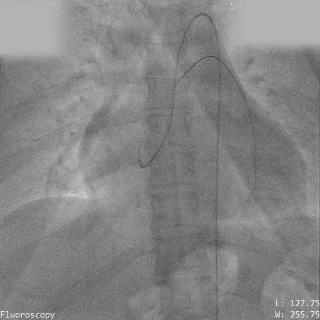

术前造影

主动脉瓣上造影,破口约5mm

轨道建立

导丝通过主动脉窦瘤破口

导丝置于下腔静脉

圈套器抓取导丝建立完整轨道